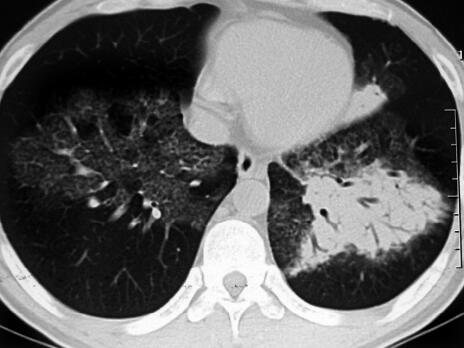

经莫西沙星治疗6天后患者仍有发热,体温稍降低,但仍可达38℃,双肺仍可闻及广泛湿啰音,双下肺可闻及散在干鸣音,气短较前加重。辅助检查回报:①血常规:白细胞计数10.5×109/L,中性粒细胞百分比85%,淋巴细胞百分比12%;②复查血清各种抗体(支原体、衣原体、军团菌)均为阴性,结核抗体阴性,PPD阴性;③痰细菌培养:未生长细菌;痰真菌培养阴性;④胸腔彩超:左侧胸腔积液;⑤胸水化验:胸腔积液常规:黄色微浊胸水,李凡他试验(+),细胞计数700×106/L;胸水生化:蛋白38.5g/L,ADA 78U/L;⑥胸部CT(治疗1周后):双肺仍可见斑片影,左肺实变影,左侧胸腔积液(图2)。

图2

患者拟诊为CAP,应用广谱抗生素莫西沙星,经过适当的抗感染治疗但病情无明显好转,此时应该考虑两个问题:①是否为特殊病原体感染?②是否是非感染性疾病?根据患者的临床特点及胸部CT表现,目前仍考虑为肺部感染性疾病,注意特殊病原体感染的可能性。患者结核抗体阴性,反复留痰查结核杆菌阴性,两次查肺炎支原体抗体、衣原体抗体、军团菌抗体阴性,以上非典型病原体感染的可能性不大,应注意其他病原感染可能,因此,重新深入询问病史特别是个人史并进行有针对性的检查非常重要。